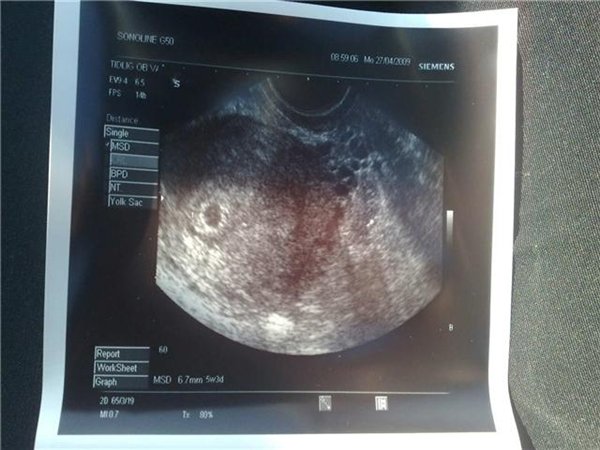

Jeg blev skannet da jeg var 5+? henne - Der kunne de ikke se noget - Så jeg fik også at vide at jeg muligvis var gravid uden for livmoderen. Fik taget blodprøver, som heller ikke steg som de burde - men da jeg blev skannet 10 dage senere, lå der en lille fis derinde, med et blinkende hjerte

- Og nu er hun en dejlig pige på 10 måneder.